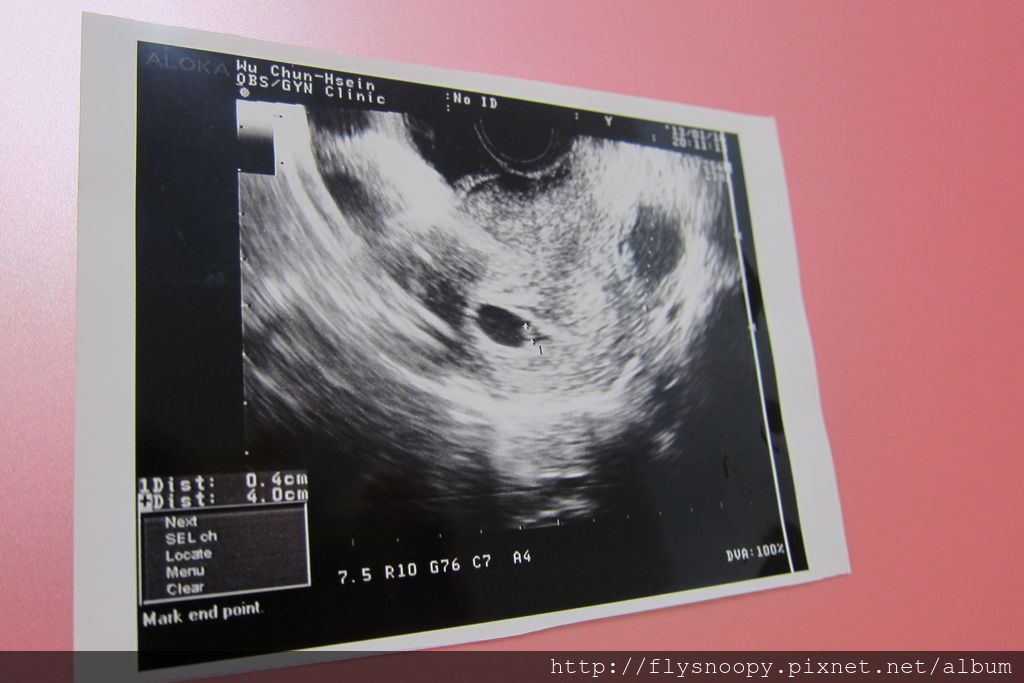

2013.1.9有褐色分泌物所以再去診所

2013.1.16也是因為有分泌物所以去看診,發現超音波照得越來越清楚囉~~~

從驗到兩條線到一月底,除了一開始有小出血外,

中間有兩次都有出現褐色分泌物,都讓我好緊張阿,